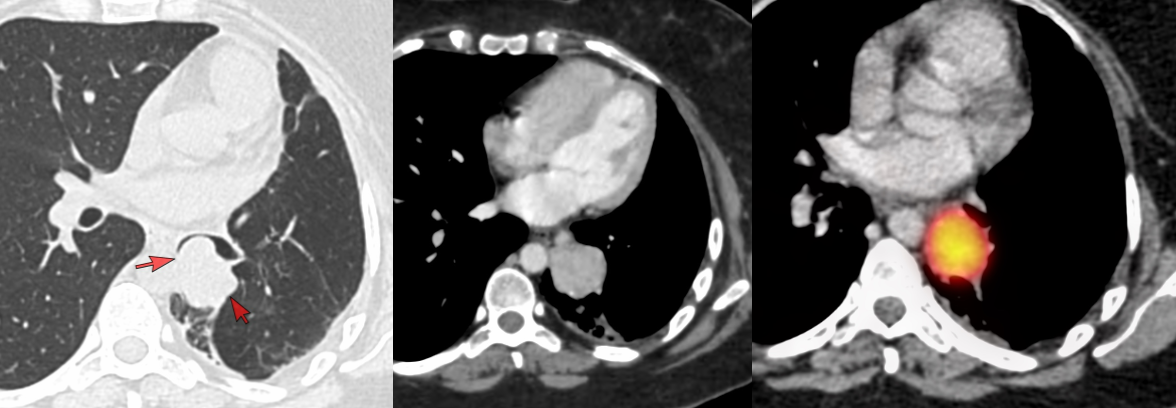

Another 30-years old had a similar tumor in the left lower lobe.

Both lesions are highly suggestive of a well-differentiated neuroendocrine tumor (NET)/carcinoid. One patient went straight to surgery while another still underwent a biopsy and then surgery.